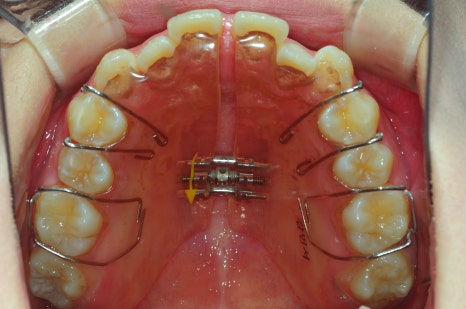

< 스마일디치과 비발치 교정 사례 >

*치료 전후 사진은 환자의 동의하에 게재하였으며, 동일한 환경과 조건에서 촬영된 전후 사진입니다.

예를 들어, 위턱이 좁아 돌출입처럼 보이는 경우,

악궁 확장 장치를 통해 턱뼈 자체를 넓혀주면,

치아가 배열될 공간이 쉽게 확보되어 비발치 교정으로도

매우 드라마틱한 얼굴형 개선이 가능합니다.